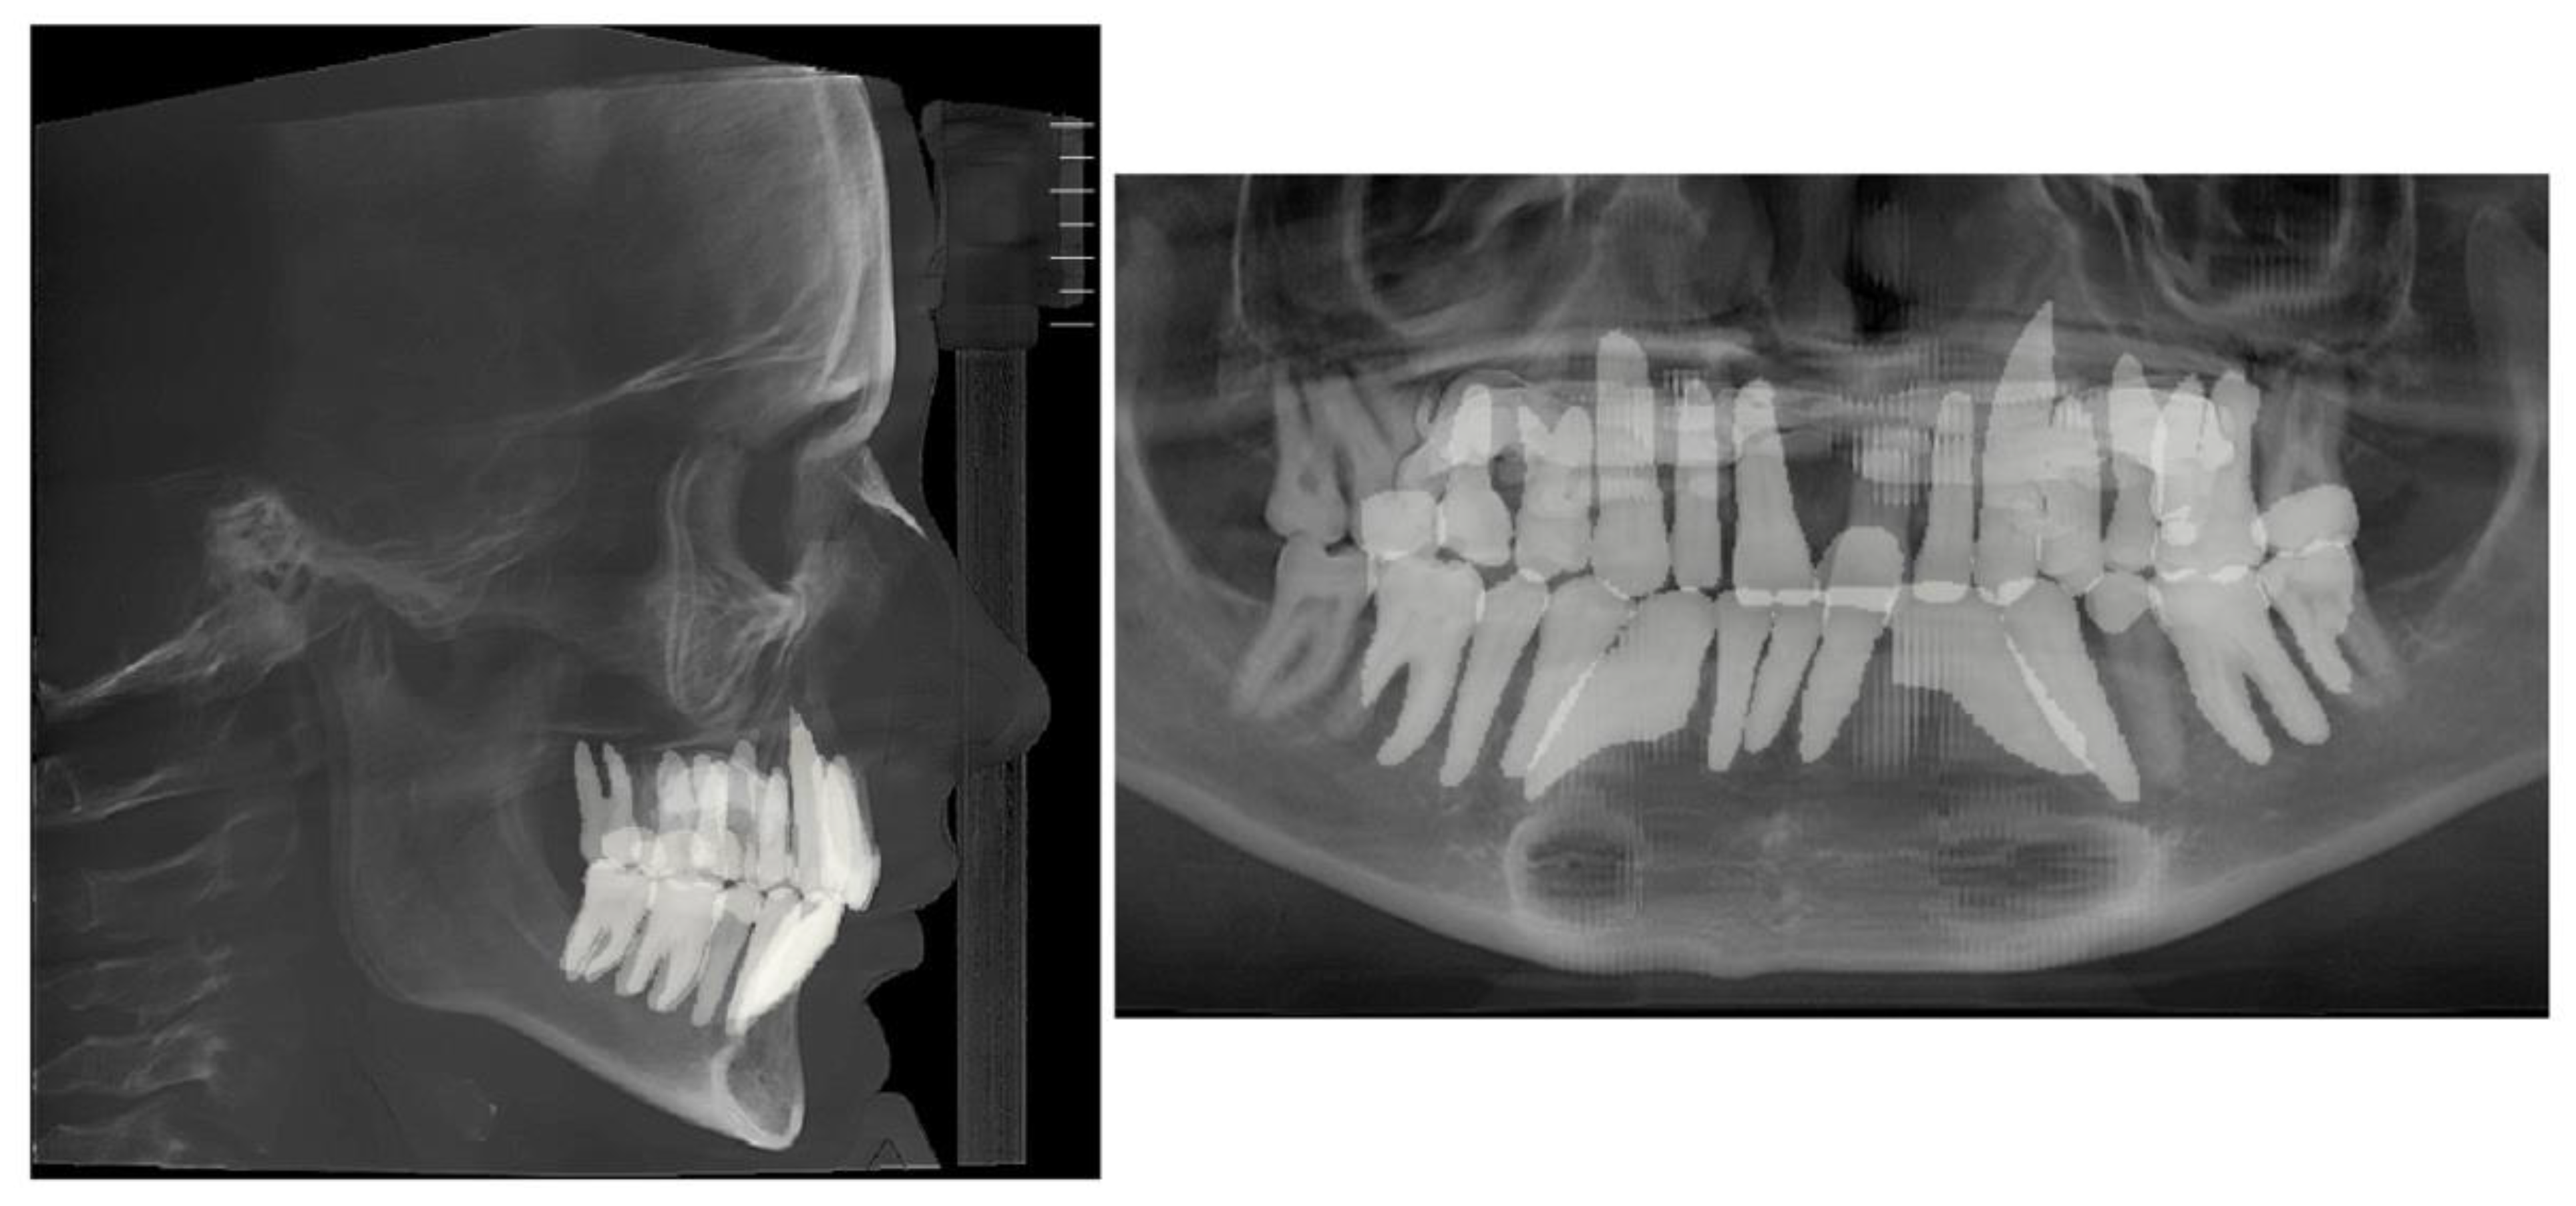

Figure 3. Pre-treatment lateral cephalometric and panoramic radiographs taken in habitual occlusion.

Lateral cephalometric radiograph and panoramic radiograph immediately after expansion shown in Figure 9.